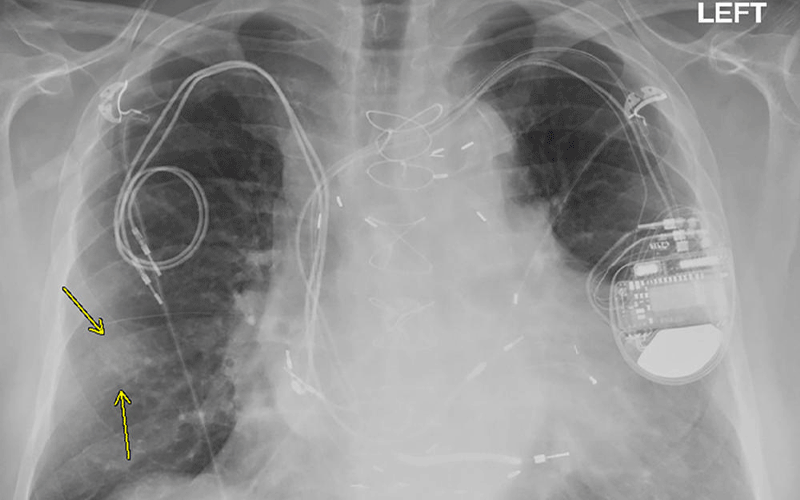

Millions of people around the world rely on implanted cardiac devices like pacemakers and implantable cardioverter defibrillators (ICDs) to help control abnormal heart rhythms. MRIs are discouraged or prohibited in many of these people over fears that the powerful magnet of the scanner will heat the metal in the devices, potentially damaging heart tissue and harming the devices.

Prior research has demonstrated the safety of performing MRI exams in patients with non-MR conditional devices. However, those studies did not account for pacemaker-dependent ICD patients. Other groups not accounted for in previous studies include patients undergoing chest and cardiac MRI exams and patients with abandoned or fractured leads.

Patients had their devices checked before and after each MRI and had their vital signs monitored closely by a nurse during their time in the scanner. Devices were turned to asynchronous mode in pacemaker-dependent patients before they went in the scanner. ICD patients had tachycardia therapies disabled during the MRI.

The results demonstrated that MRI exams—including chest MRI exams—can be performed safely in pacemaker-dependent ICD patients and in patients with non-MR conditional devices or abandoned leads.